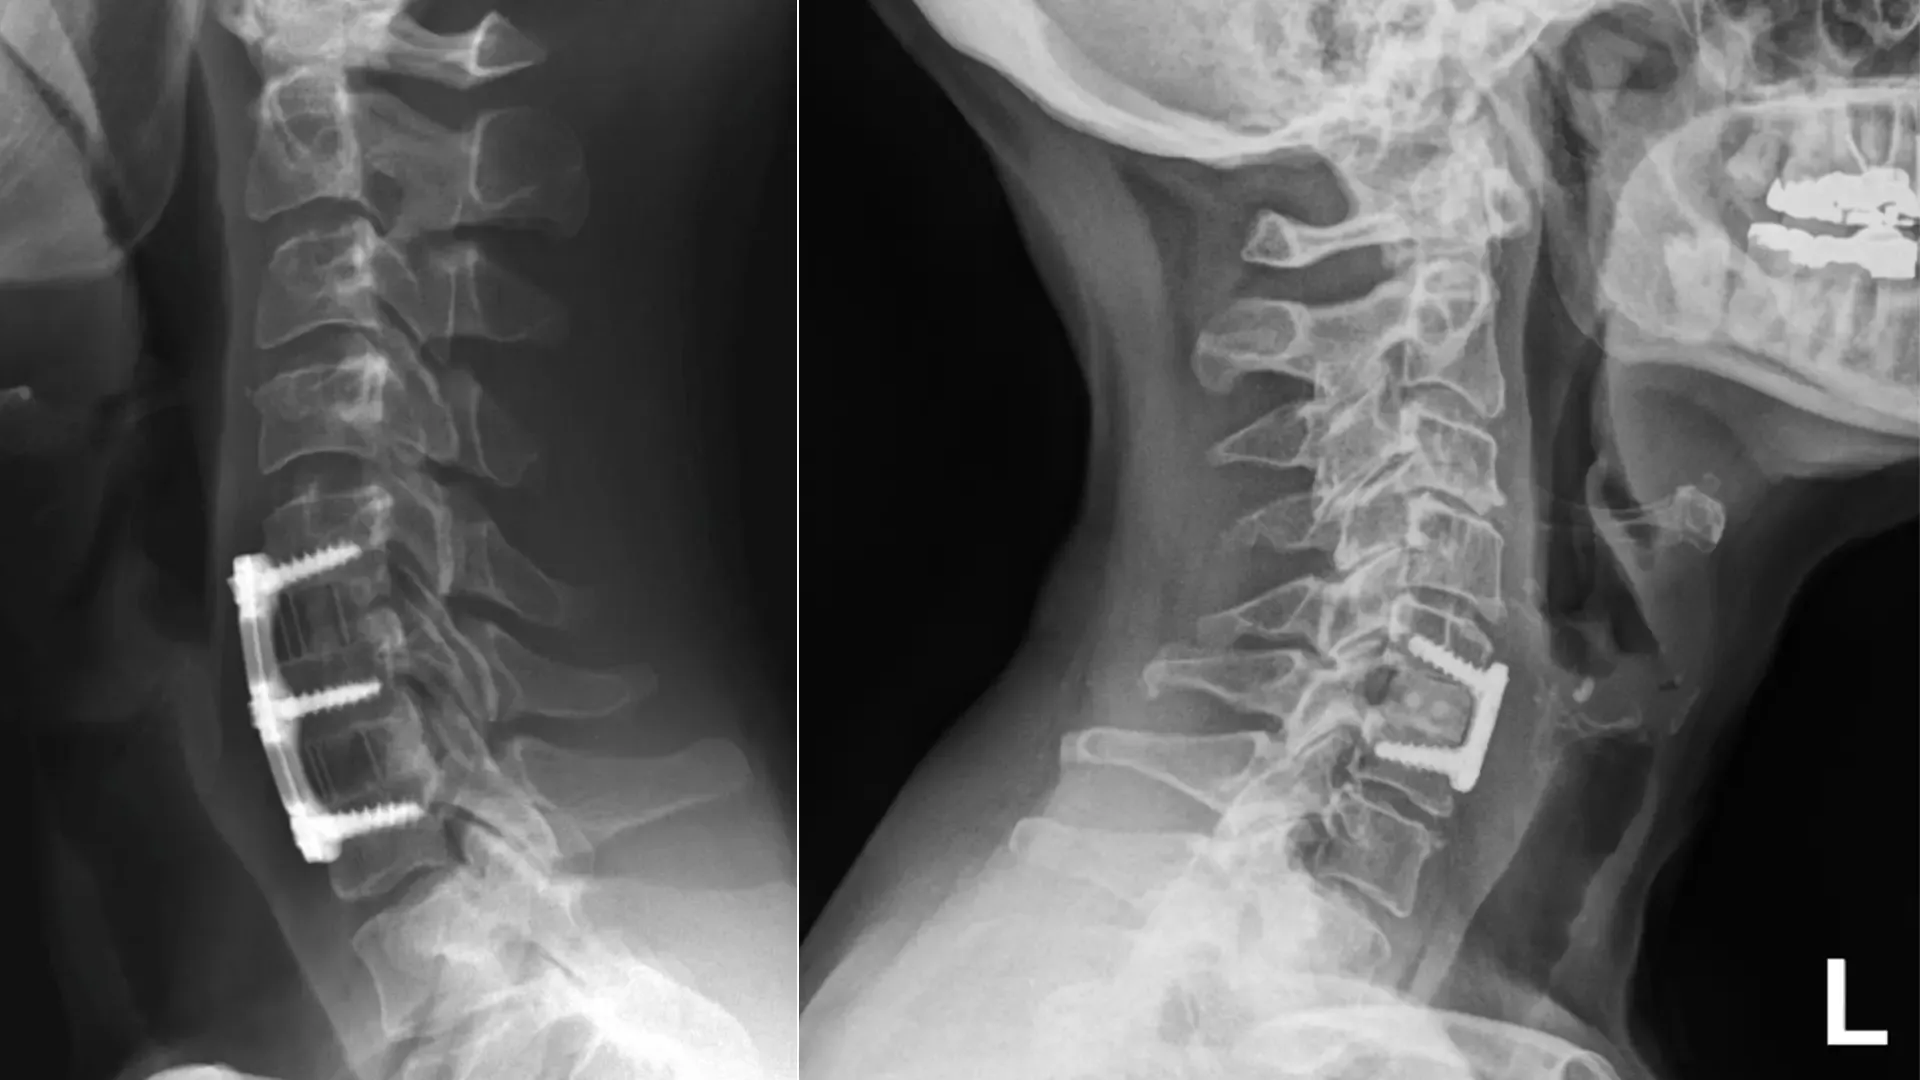

柳營奇美醫院神經外科醫生呂忠哲經詳細評估,判斷是頸椎脊髓神經病變導致下肢無力的症狀,隨即安排住院檢查,在磁力共振掃描檢查顯示,頸椎椎間盤突出壓迫脊髓神經,已被壓到只剩一條極細的通道,神經因缺血已變色,情況十分危急,因此立即安排手術,清除壓迫神經的椎間盤,並針對頸椎滑脫進行融合固定。

頸椎手術方式多樣,目前主流方式包括人工椎間盤置換術和頸椎融合固定術。兩者主要差異在於人工椎間盤置換術保留頸椎活動性、復原較快,但不適合骨質疏鬆或脊椎滑脫的患者;頸椎融合固定術則適用於結構不穩定的情況,但術後活動角度較差。因此醫生會根據病情與病人討論,並選擇適合的治療方式,有效改善症狀並提升生活質素。